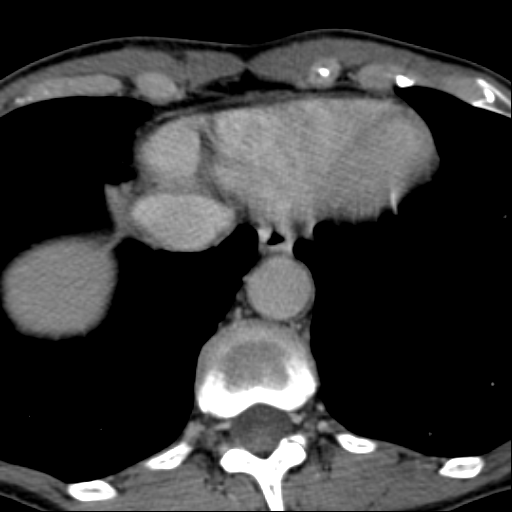

Обнаружилось небольшое образование низкой плотности, с достаточно ровными, четкими контурами парааортально справа около ножки диафрагмы на уровне тела L1 позвонка.

При нативе плотность 6HU, паренхиматозная - 18-20HU, экскреторная (15 минут) - 60-65HU.

Выкладываю по очереди срезы на одинаковых уровнях, сначала паренхиматозная, потом отсроченная фазы.

или я придираюсь или там что-то под правой почкой есть!!! сканограм побольше бы?!!!! можно еще немного кадров корон в венозную фазу выложить????

Позвонил сейчас на работу, не выдержал. Коллега посмотрела - петля тонкой кишки 100%.